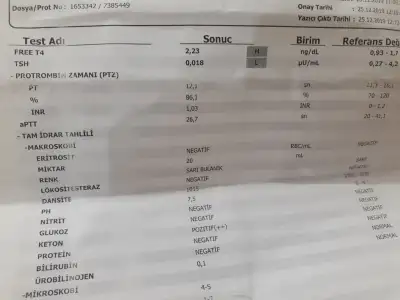

Benimde dusuklerin sebebi tiroid dedi dr ilk günden beri kullanıyorum dahiliyeye yönlendirdi hatta dozu artırdı tabi kafanı karıştırmak için söylemiyorum her drun ne son göre bi bildiği oluyo allahım şifa versin ins